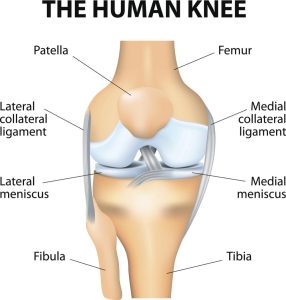

We have ligaments in our body that connect one bone to another bone. All bones in your body are held together by these fibrous connective tissues. Your knee joint has four of these ligaments. They are Anterior Cruciate Ligament (ACL), Posterior Cruciate Ligament (PCL), Lateral Collateral Ligament (LCL) and Medial Collateral Ligament (MCL).